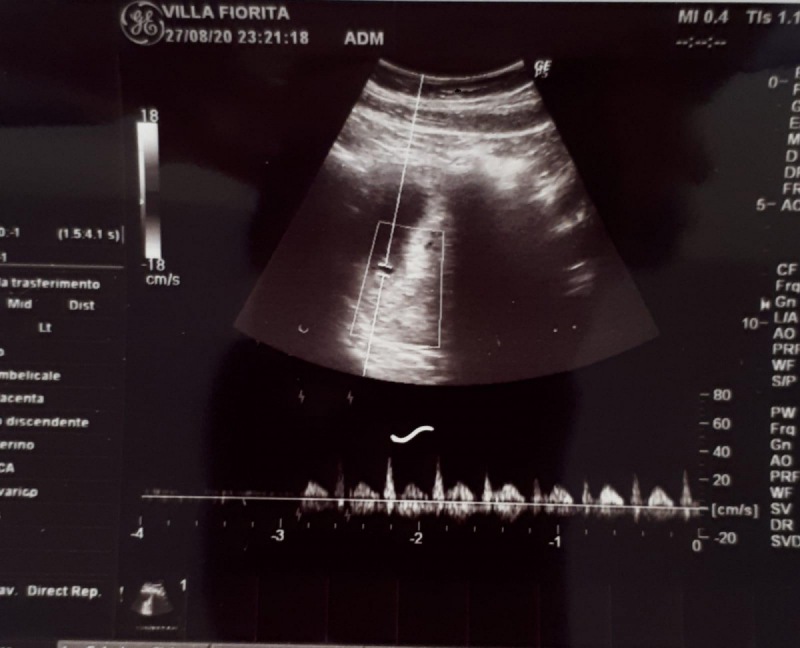

"Eccezionale intervento oncologico su una ragazza in stato interessante presso la Casa di Cura Villa Fiorita di Capua. Una giovane donna al secondo mese di gravidanza, è stata sottoposta, nei giorni scorsi, ad un’operazione chirurgica per la asportazione di una voluminosa massa alla mammella che stava crescendo con il progredire della gestazione.-spiega la nota-L'èquipe chirurgica, guidata dal Responsabile della Chirurgia Oncologica, Crescenzo Muto, ha asportato la massa senza particolari complicanze e la paziente è stata dimessa già il giorno successivo. “Lo straordinario intervento è stato reso possibile dalla stretta collaborazione con l'equipe

anestesiologica, che ha provveduto al monitoraggio intraoperatorio, e grazie -si legge nella nota-al reparto di ostetricia che ha monitorato la gravidanza per scongiurare eventuali problemi al nascituro”, ha dichiarato il chirurgo oncologo Muto. “Ancora un brillante risultato che deriva dalle professionalità e dalla collaborazione tra specialisti che lavorano nella nostra Clinica, sempre più punto di riferimento per i pazienti di Terra di Lavoro e delle altre zone della Campania e del basso Lazio”, dichiara Raffaella Sibillo, Presidente del CdA della Casa di Cura Villa Fiorita di Capua."